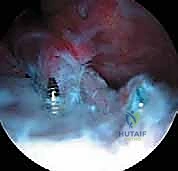

- التكنولوجيا المتقدمة: ريادته في استخدام أحدث التقنيات الطبية في اليمن، بما في ذلك الجراحة الميكروسكوبية الدقيقة (Microsurgery)، وجراحة مناظير المفاصل عالية الدقة (Arthroscopy 4K)، وعمليات تغيير المفاصل (Arthroplasty).

بعد اكتمال التشخيص وتحديد نوع الكسر بدقة، يقوم الأستاذ الدكتور محمد هطيف بالجلوس مع الوالدين لشرح الخيارات العلاجية المتاحة بشفافية تامة. الهدف الأساسي من العلاج هو إعادة القطعة العظمية إلى مكانها التشريحي الطبيعي (الرد) وتثبيتها حتى تلتئم، وذلك لاستعادة الشد الطبيعي للرباط الصليبي الأمامي وضمان استقرار الركبة.

| آلية العلاج | شفط الدم من الركبة، ثم وضع الساق في جبس أسطواني (Cylinder Cast) أو دعامة صلبة في وضعية التمدد (أو انثناء طفيف 10-20 درجة). | إرجاع العظمة المكسورة لمكانها وتثبيتها ميكانيكياً باستخدام خيوط جراحية قوية أو مسامير طبية. |

| المزايا (الإيجابيات) | تجنب مخاطر التخدير العام والجراحة، تكلفة أقل، عدم وجود ندبات. | رد تشريحي مثالي ودقيق، استقرار فوري أقوى للركبة، القدرة على معالجة الإصابات المصاحبة (مثل خياطة الغضروف الهلالي الممزق في نفس الوقت). |

| العيوب (السلبيات) | خطر تحرك الكسر داخل الجبس (فقدان الرد)، تيبس الركبة بسبب طول فترة التثبيت، احتمالية بقاء الركبة رخوة إذا لم يلتئم العظم بشكل مثالي. | يتطلب تخديراً عاماً، تكلفة أعلى، يتطلب جراحاً ذا مهارة عالية جداً (خاصة لتجنب إصابة صفائح النمو). |